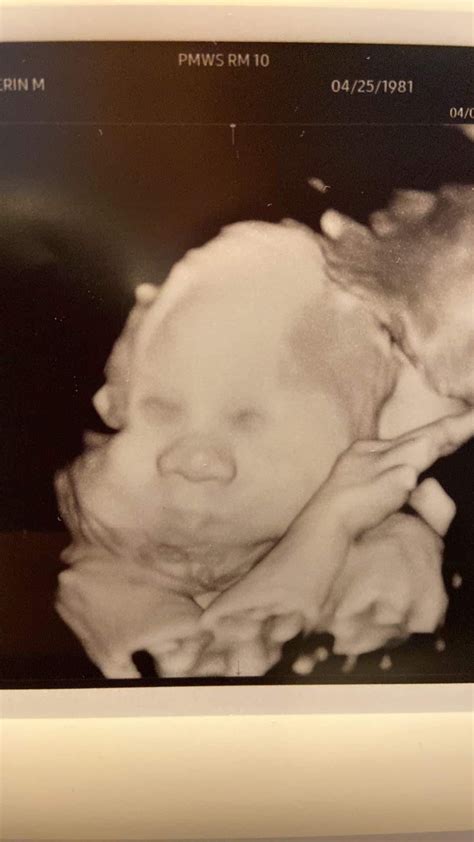

Because your baby is now larger and there is less amniotic fluid relative to the baby’s size compared to the second trimester, the images may look a bit different. You might notice your baby's features more clearly, such as the face, limbs, and movements. It is an excellent time to witness your baby practicing breathing movements, sucking their thumb, or even yawning.

Beyond the medical necessity, this scan is often an emotional highlight. Seeing your baby at 32 weeks makes the reality of pending parenthood feel much more tangible. You may be able to see distinctive features, and if your baby is positioned well, you might get a clear view of their face. Many parents choose to print or digitally save these images as a cherished keepsake, marking the final stretch of their pregnancy journey.